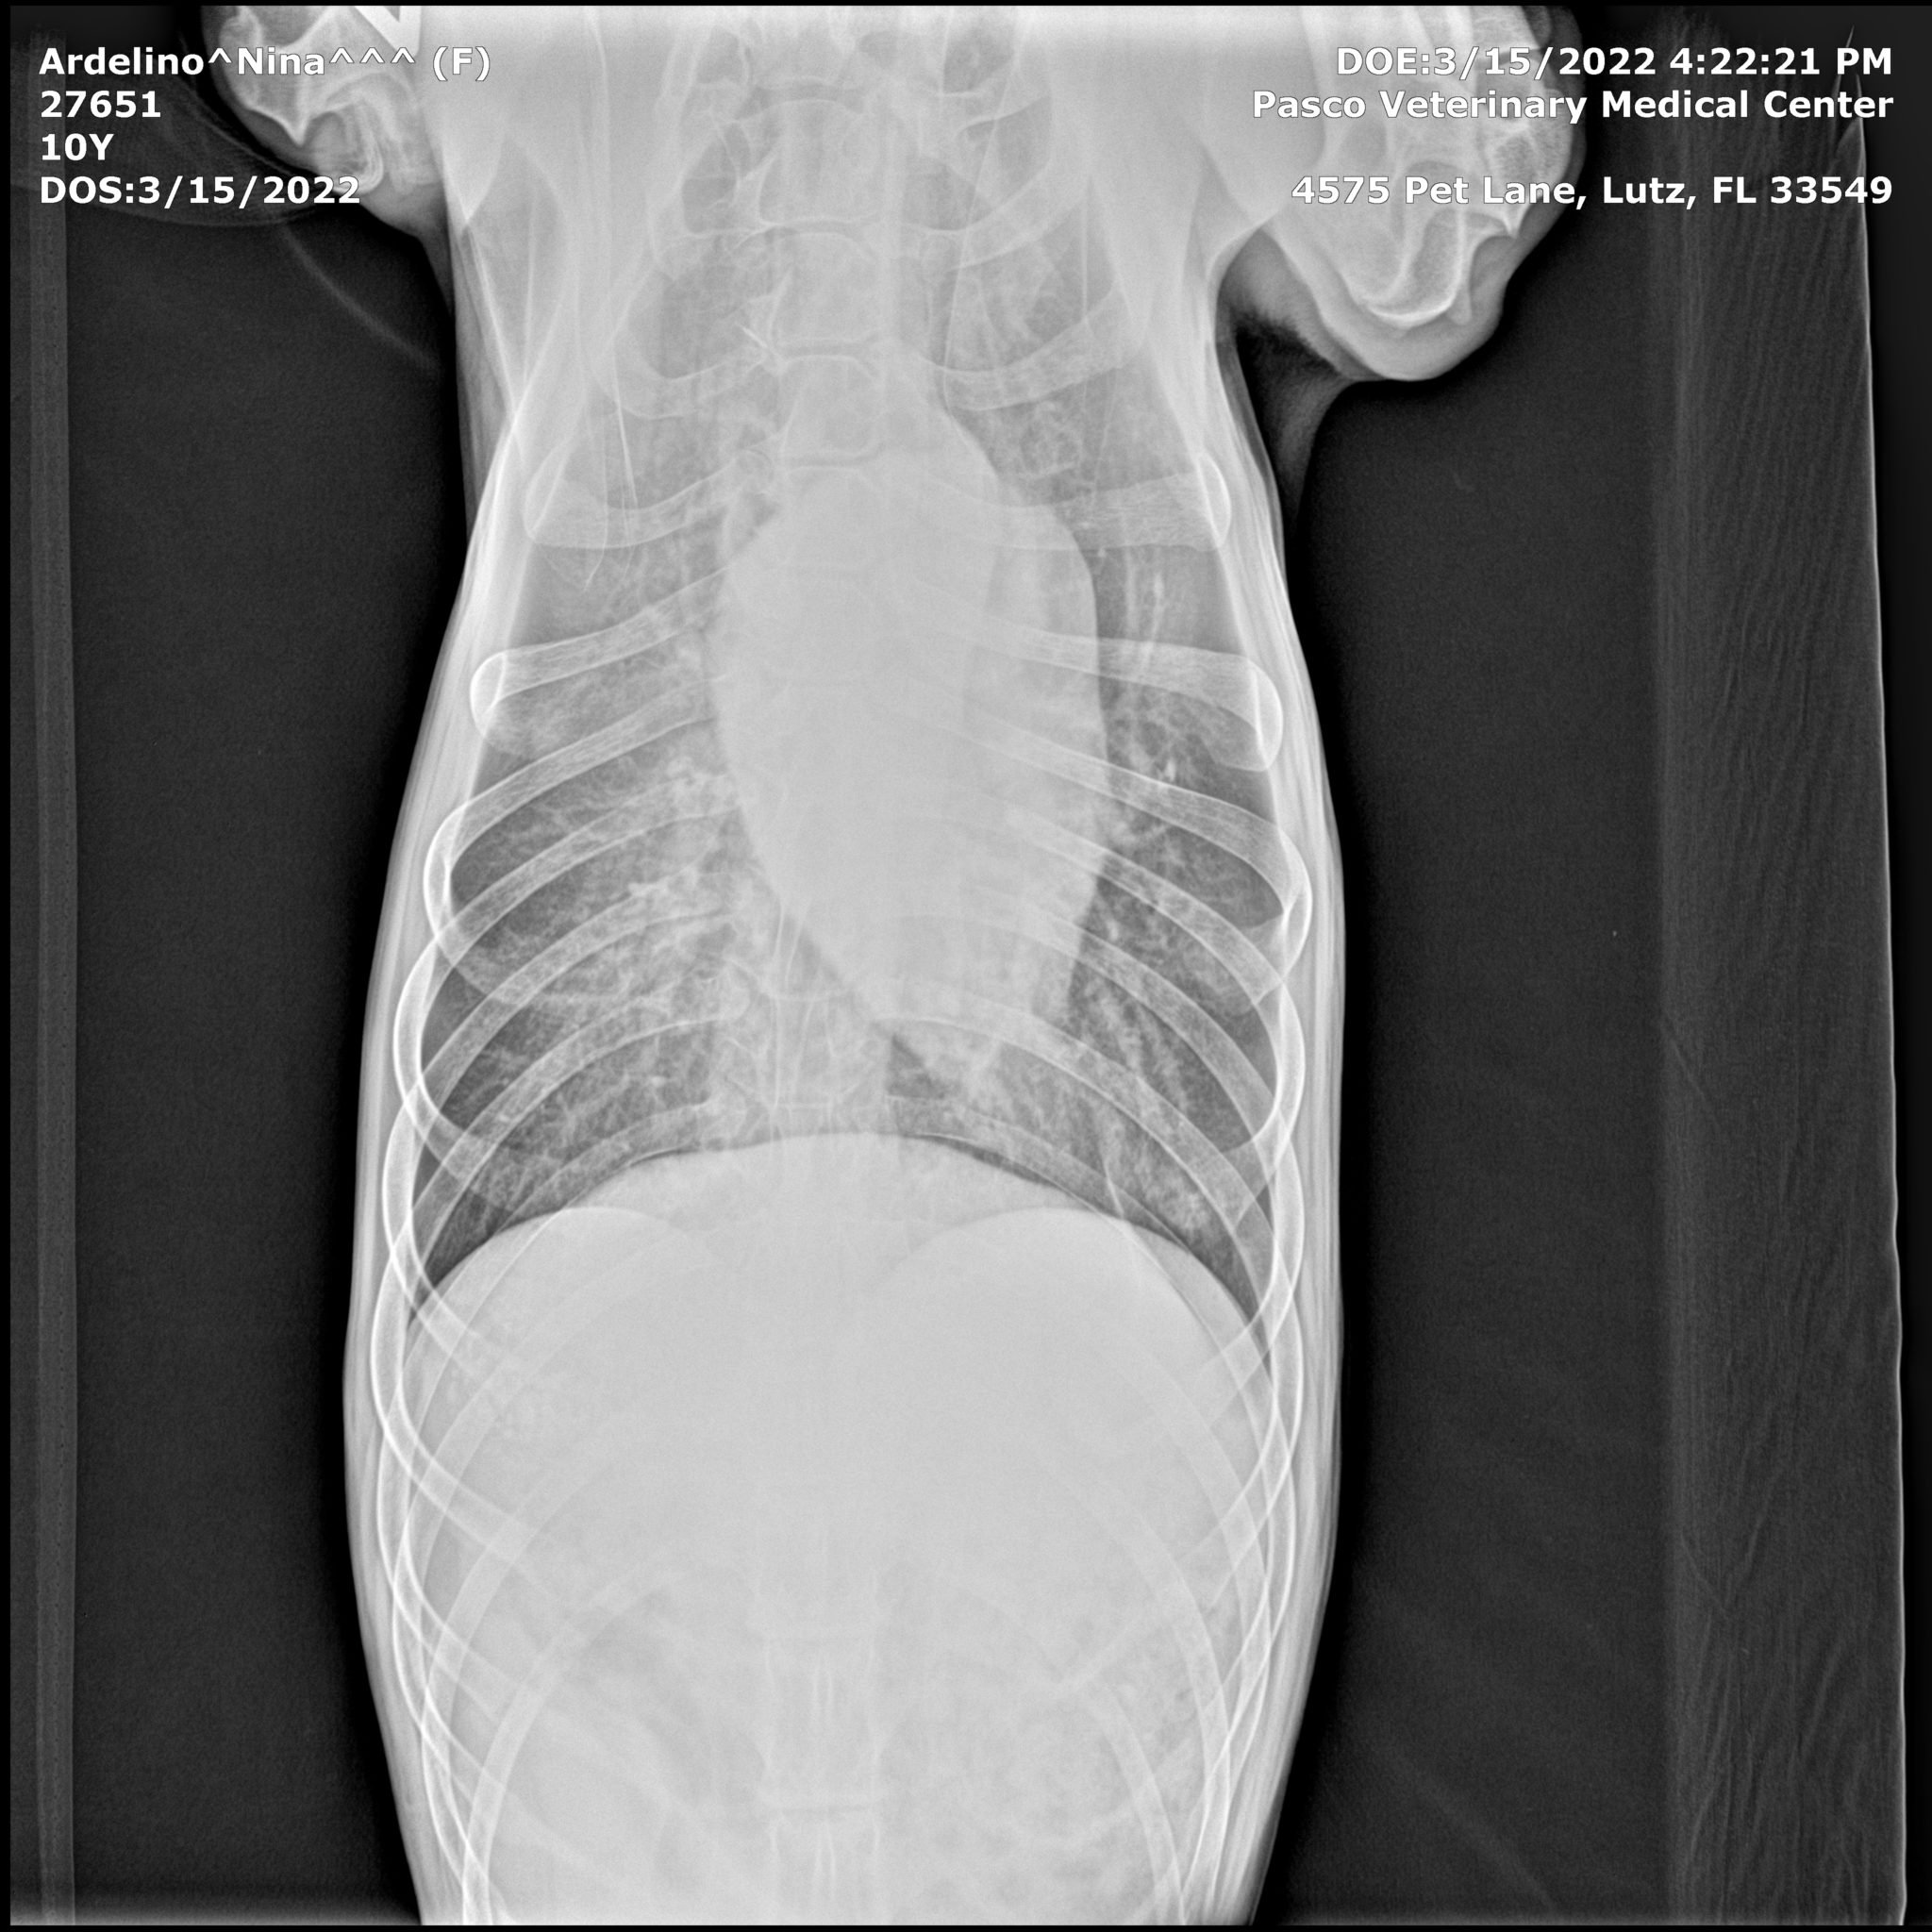

Here are Nina’s X-rays, showing no metastasis, no spread of cancer 22 months post diagnosis of osteosarcoma in dogs:

The tumor had grown to the size of a grapefruit, and was cutting off circulation to her foot. It had also started to seep fluids, through a small sore on the surface of the growth. This meant that we would once again run all the diagnostic tests again to see if, after 22 months, the cancer had metastasized.

The results were what we’d hoped for! No Metastasis! Once again there was NO SPREAD of cancer anywhere else in her body.